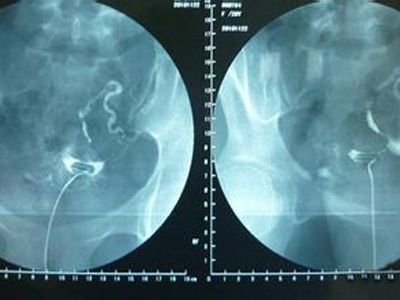

第三步、在X线透视下观察造影剂流经宫腔,在荧光的透视下慢慢注入碘油,注入量次为3~5ml,观察其进入子宫及流经输卵管的情况,此时会拍摄一张照片然后会继续推入碘油,5--10分钟后继续拍片。

第四步、一天之后再在同部位拍摄,然后观察腹腔内是否有游离的碘海醇,如果双侧输卵管不通,那么盆腔内就不会有碘油,如果只有少量碘海醇那么久可以认为是输卵管通而不畅。